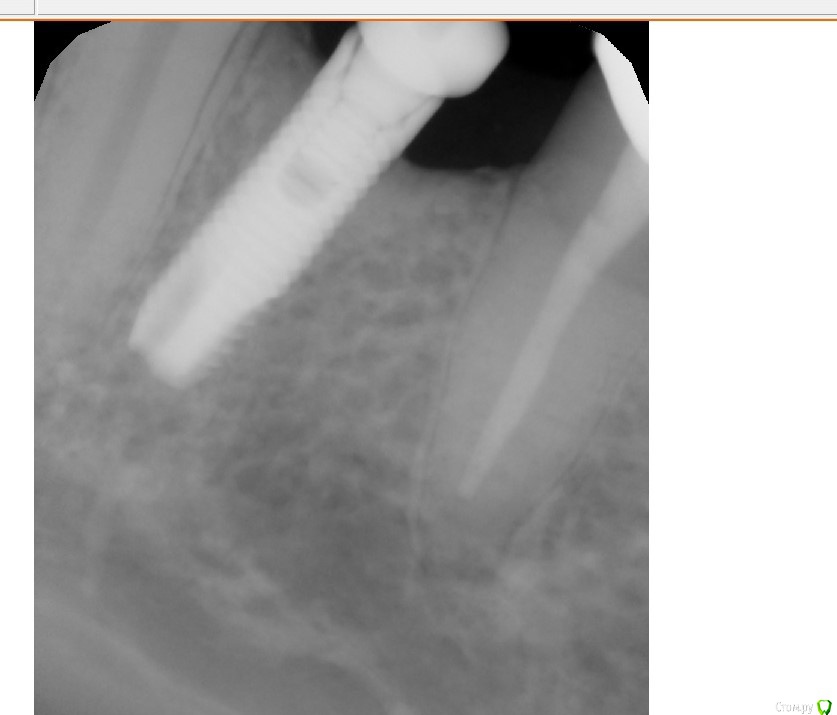

Коллеги добрый вечер. Может кто узнает систему - очень надо, со слов пациента ставил 10 лет назад. Внешне размер платформы примерно 3.5 мм, ключ подошел корейский 1.2, формирователь закрутилс(хоть и не до конца) от Osstem mini/ Внешне напоминает xive или antogyr. Буду очень благодарен.